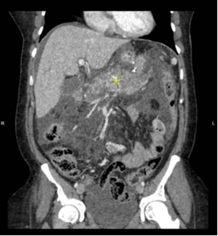

clinical condition and worsening lactic acidosis, repeat STAT CT abdomen and

pelvis was performed, which showed necrotizing pancreatitis (Figure 2),

large loculated ascites and bilateral pleural effusion with lower lobe

atelectasis.

Figure 2: CT scan showing pancreatic

necrosis (Yellow arrow)